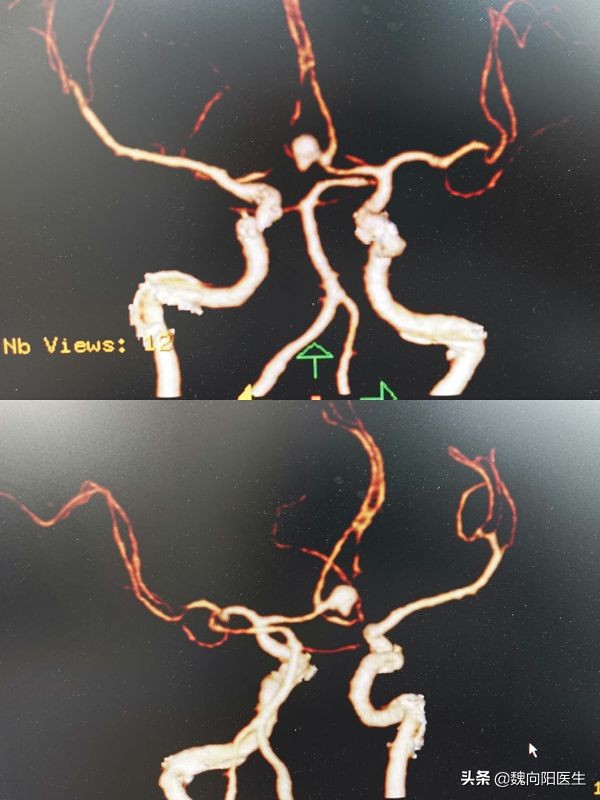

赶紧拉到医院,头CT提示:蛛网膜下腔出血。

这可是一个要命的病,一般都是由于脑动脉瘤破裂所导致。

动脉瘤破裂之后,会涌出大量的新鲜血液,使大脑浸泡在血水当中。随时间的推移,这些血水会持续的毒害大脑,导致一系列的反应。